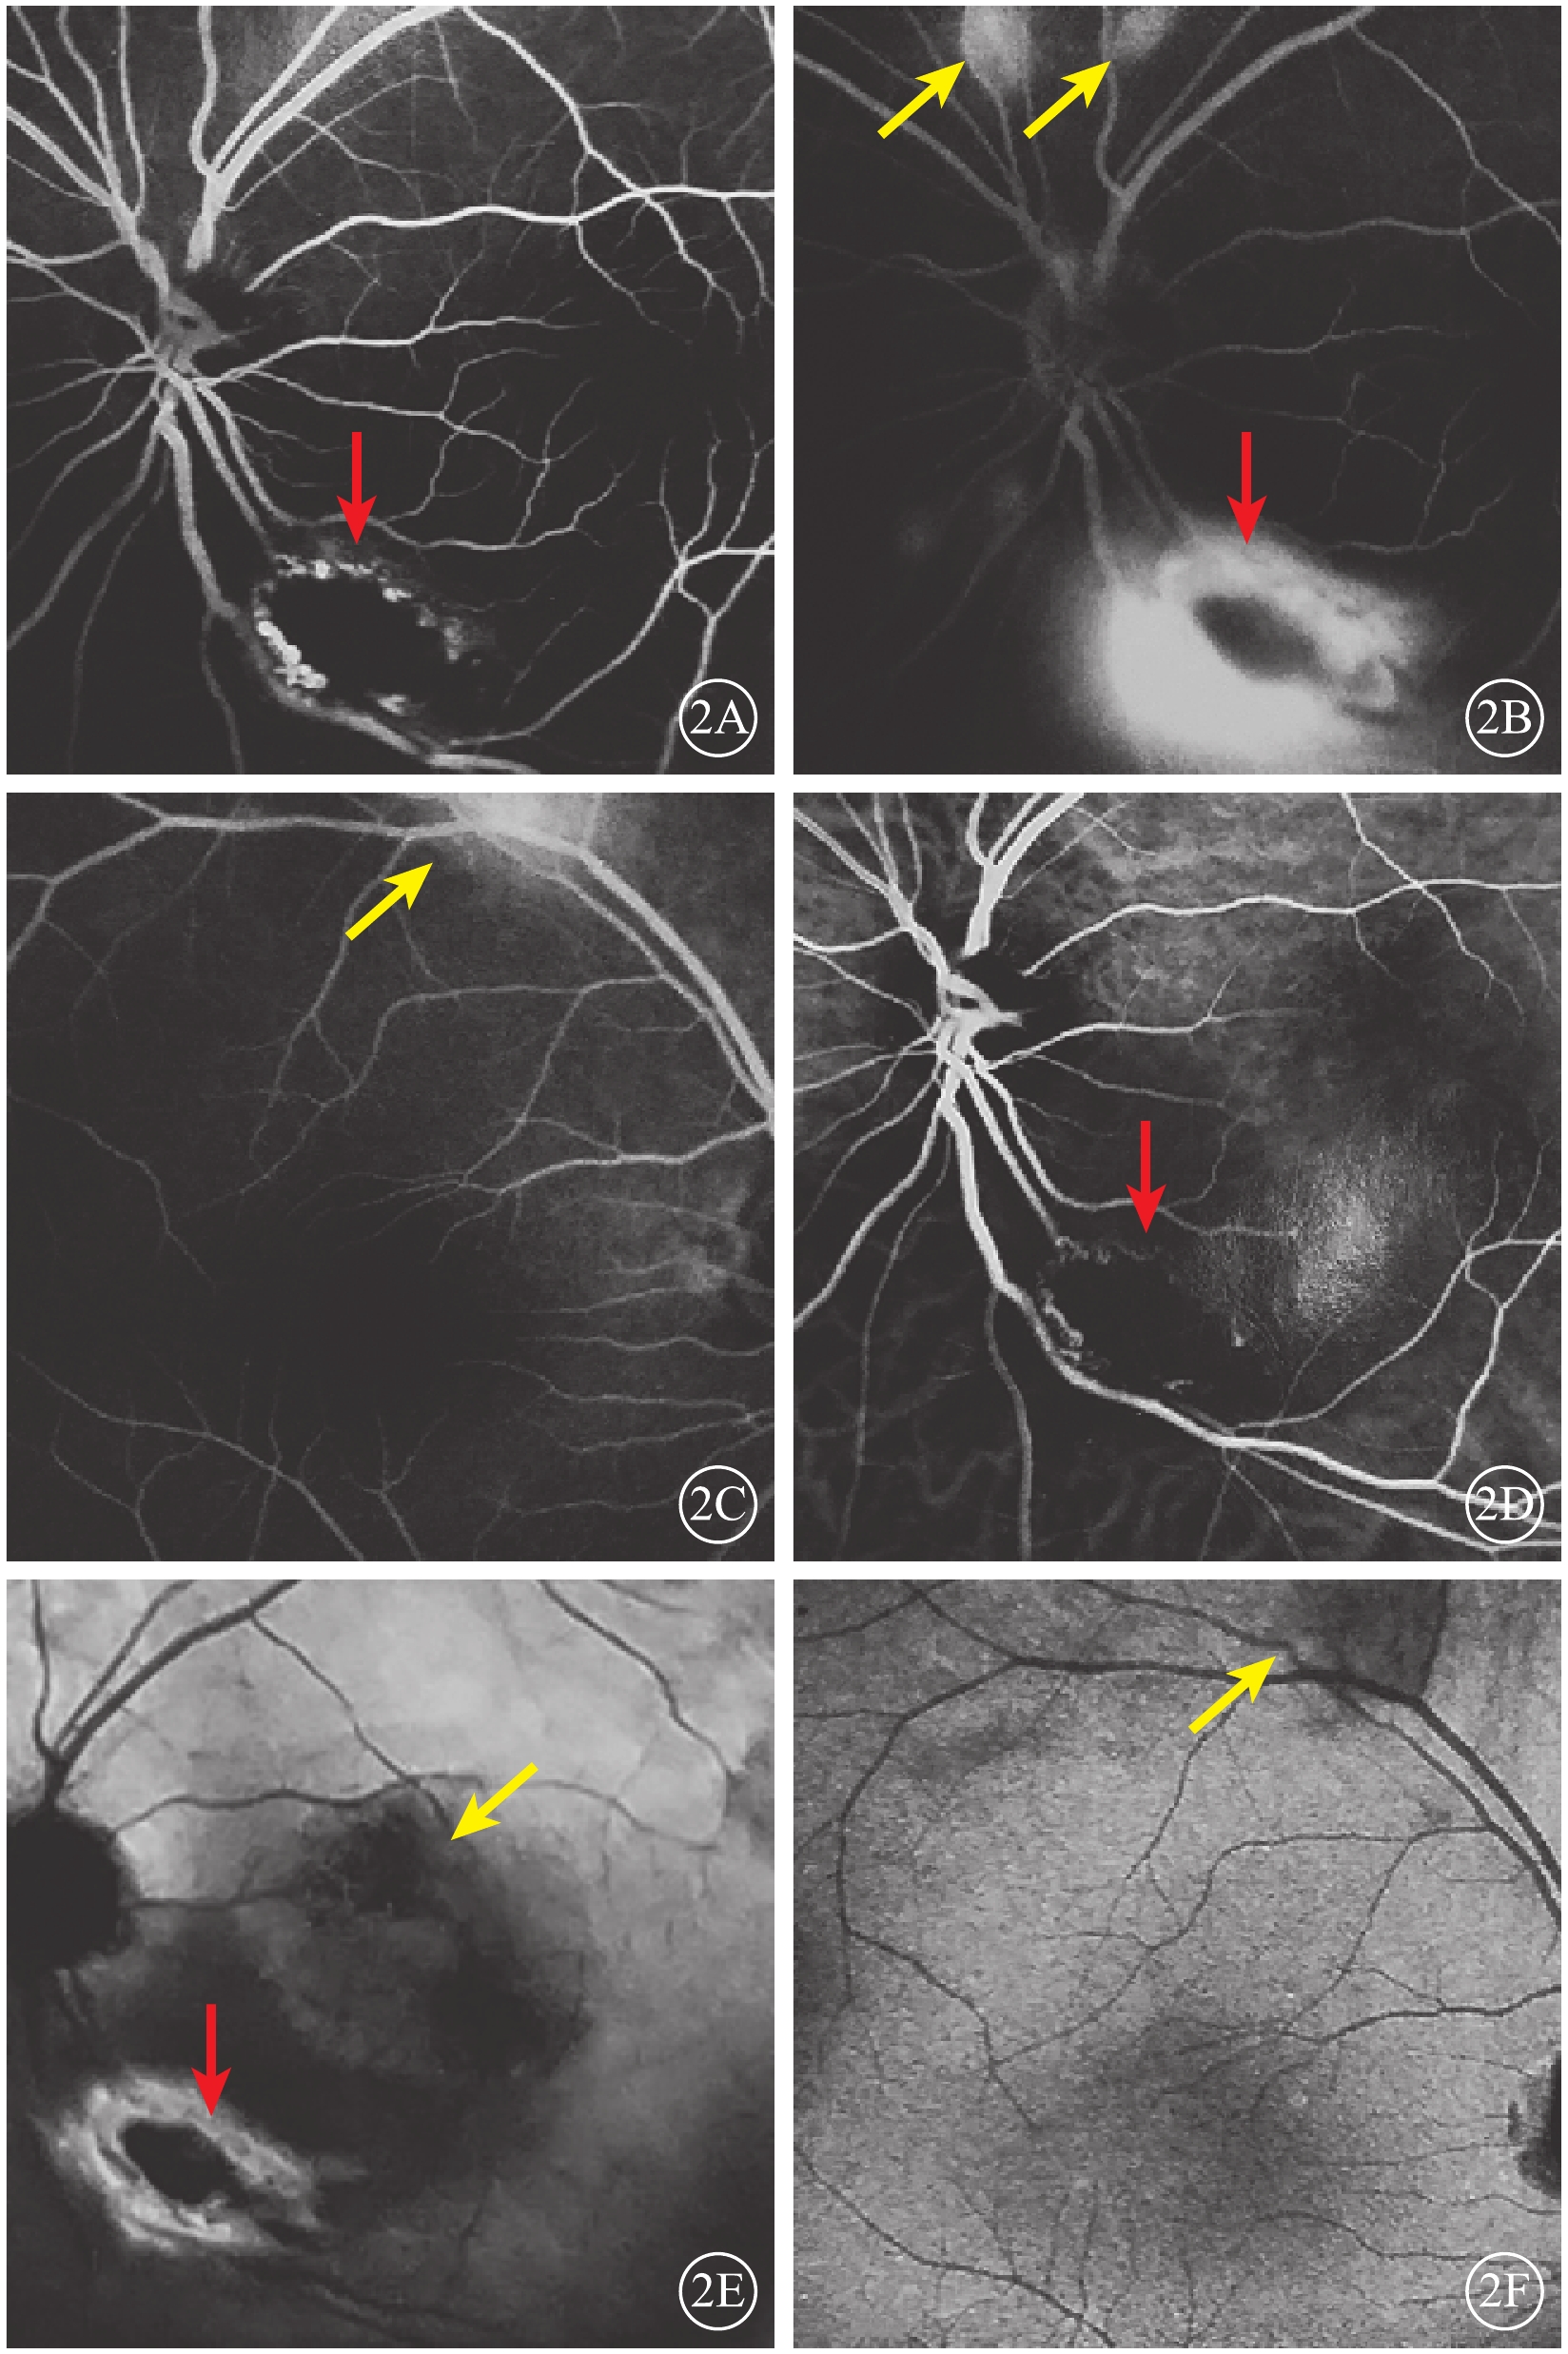

眼部檢查:右眼裸眼視力0.8,矯正視力1.0;左眼裸眼視力0.15,矯正不能提高。雙眼眼壓及眼前節檢查正常。眼底檢查,左眼視盤下方可見大小約1/2個視盤直徑(DD)的局限性黃白色隆起病灶,其周圍滲出性視網膜脫離。右眼眼底無異常。外院熒光素眼底血管造影(FFA)檢查,左眼早期視盤顳下方約1 DD大小的橢圓形弱熒光,周圍環繞不均勻強熒光,黃斑區廣泛彌漫弱熒光,視盤上方兩處1/4 DD大小、顳上血管弓處兩處1/2 DD大小橢圓形稍強熒光(圖2A);晚期各病灶熒光素滲漏明顯,邊界不清(圖2B)。右眼上方血管弓處1/2 DD大小病灶早期稍強熒光,晚期熒光素滲漏(圖2C)。吲哚青綠血管造影(ICGA)檢查,左眼早期視盤顳下弱熒光,周邊環繞強熒光環(圖2D);晚期病灶周圍熒光素滲漏,邊界不清(圖2E),其余FFA檢查可見的病灶在ICGA上未見明顯異常熒光。右眼早晚期均可見上方血管弓處片狀弱熒光(圖2F)。

圖2

患者雙眼眼底血管造影像。2A. 左眼FFA早期,視盤顳下方約1 DD大小橢圓形弱熒光,周圍環繞不均勻強熒光(紅箭);2B. 左眼FFA晚期,視盤上方兩處1/4 DD大小病灶熒光素滲漏明顯(黃箭),視盤下方病灶熒光素滲漏邊界不清(紅箭);2C. 右眼FFA晚期,上方血管弓處可見熒光素滲漏(黃箭);2D. 左眼ICGA早期,視盤顳下早期弱熒光病灶,周邊繞以強熒光環(紅箭);2E. 左眼ICGA晚期,視盤下方病灶周圍熒光素滲漏,邊界不清(紅箭),黃斑區強弱熒光混雜(綠箭);2F. 右眼ICGA晚期,上方血管弓處片狀弱熒光(黃箭)

圖2

患者雙眼眼底血管造影像。2A. 左眼FFA早期,視盤顳下方約1 DD大小橢圓形弱熒光,周圍環繞不均勻強熒光(紅箭);2B. 左眼FFA晚期,視盤上方兩處1/4 DD大小病灶熒光素滲漏明顯(黃箭),視盤下方病灶熒光素滲漏邊界不清(紅箭);2C. 右眼FFA晚期,上方血管弓處可見熒光素滲漏(黃箭);2D. 左眼ICGA早期,視盤顳下早期弱熒光病灶,周邊繞以強熒光環(紅箭);2E. 左眼ICGA晚期,視盤下方病灶周圍熒光素滲漏,邊界不清(紅箭),黃斑區強弱熒光混雜(綠箭);2F. 右眼ICGA晚期,上方血管弓處片狀弱熒光(黃箭)

眼部檢查:右眼裸眼視力0.8,矯正視力1.0;左眼裸眼視力0.15,矯正不能提高。雙眼眼壓及眼前節檢查正常。眼底檢查,左眼視盤下方可見大小約1/2個視盤直徑(DD)的局限性黃白色隆起病灶,其周圍滲出性視網膜脫離。右眼眼底無異常。外院熒光素眼底血管造影(FFA)檢查,左眼早期視盤顳下方約1 DD大小的橢圓形弱熒光,周圍環繞不均勻強熒光,黃斑區廣泛彌漫弱熒光,視盤上方兩處1/4 DD大小、顳上血管弓處兩處1/2 DD大小橢圓形稍強熒光(圖2A);晚期各病灶熒光素滲漏明顯,邊界不清(圖2B)。右眼上方血管弓處1/2 DD大小病灶早期稍強熒光,晚期熒光素滲漏(圖2C)。吲哚青綠血管造影(ICGA)檢查,左眼早期視盤顳下弱熒光,周邊環繞強熒光環(圖2D);晚期病灶周圍熒光素滲漏,邊界不清(圖2E),其余FFA檢查可見的病灶在ICGA上未見明顯異常熒光。右眼早晚期均可見上方血管弓處片狀弱熒光(圖2F)。

圖2

患者雙眼眼底血管造影像。2A. 左眼FFA早期,視盤顳下方約1 DD大小橢圓形弱熒光,周圍環繞不均勻強熒光(紅箭);2B. 左眼FFA晚期,視盤上方兩處1/4 DD大小病灶熒光素滲漏明顯(黃箭),視盤下方病灶熒光素滲漏邊界不清(紅箭);2C. 右眼FFA晚期,上方血管弓處可見熒光素滲漏(黃箭);2D. 左眼ICGA早期,視盤顳下早期弱熒光病灶,周邊繞以強熒光環(紅箭);2E. 左眼ICGA晚期,視盤下方病灶周圍熒光素滲漏,邊界不清(紅箭),黃斑區強弱熒光混雜(綠箭);2F. 右眼ICGA晚期,上方血管弓處片狀弱熒光(黃箭)

圖2

患者雙眼眼底血管造影像。2A. 左眼FFA早期,視盤顳下方約1 DD大小橢圓形弱熒光,周圍環繞不均勻強熒光(紅箭);2B. 左眼FFA晚期,視盤上方兩處1/4 DD大小病灶熒光素滲漏明顯(黃箭),視盤下方病灶熒光素滲漏邊界不清(紅箭);2C. 右眼FFA晚期,上方血管弓處可見熒光素滲漏(黃箭);2D. 左眼ICGA早期,視盤顳下早期弱熒光病灶,周邊繞以強熒光環(紅箭);2E. 左眼ICGA晚期,視盤下方病灶周圍熒光素滲漏,邊界不清(紅箭),黃斑區強弱熒光混雜(綠箭);2F. 右眼ICGA晚期,上方血管弓處片狀弱熒光(黃箭)